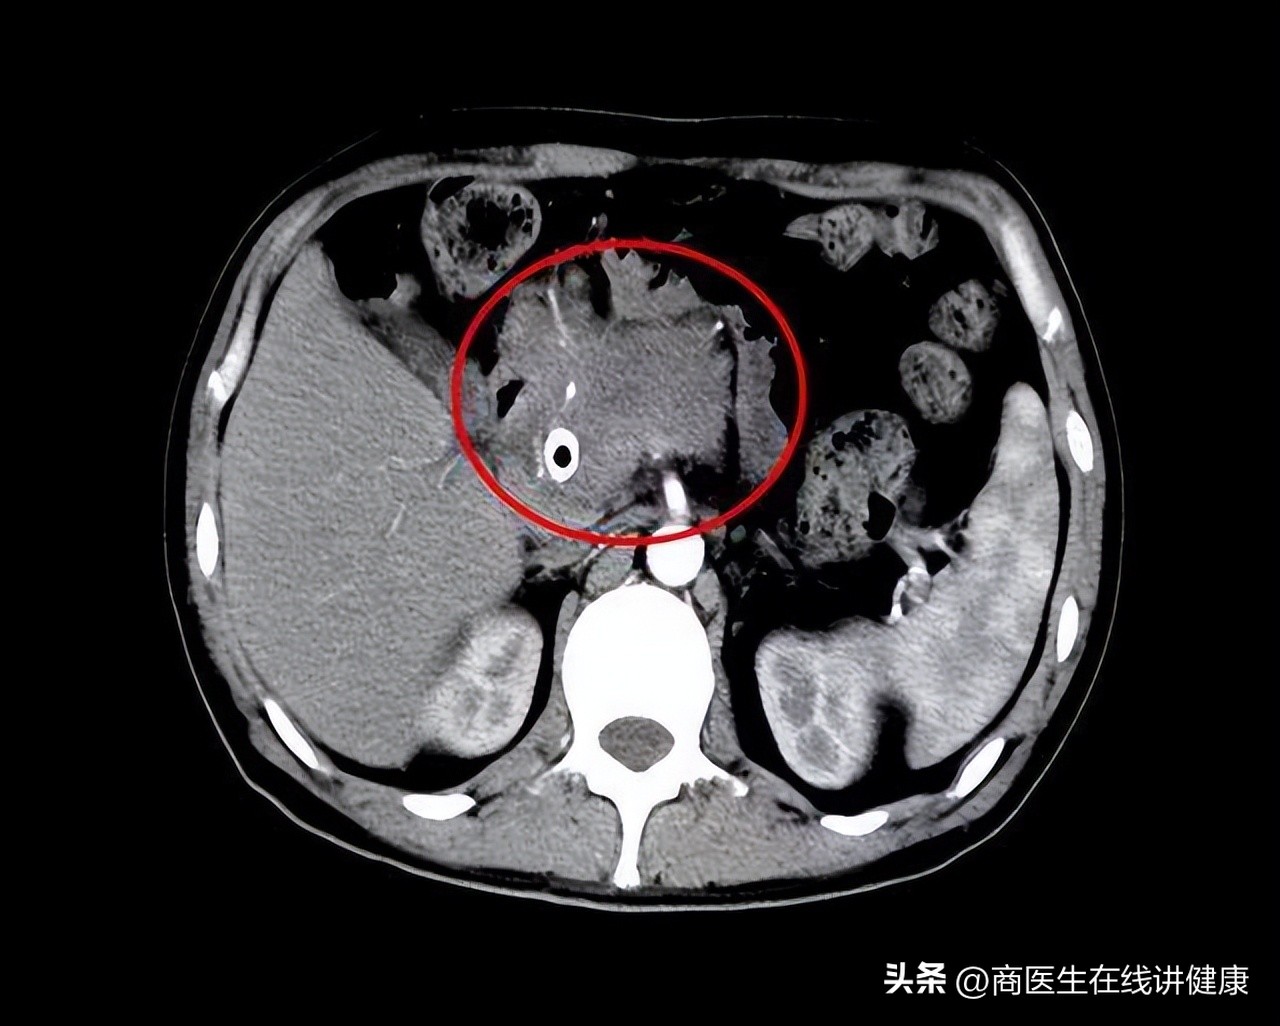

随后通过腹部CT检查平扫胰腺部位,发现胰腺腔内现病灶;

三期增强扫描CT发现病灶出现淋巴结转移现象;